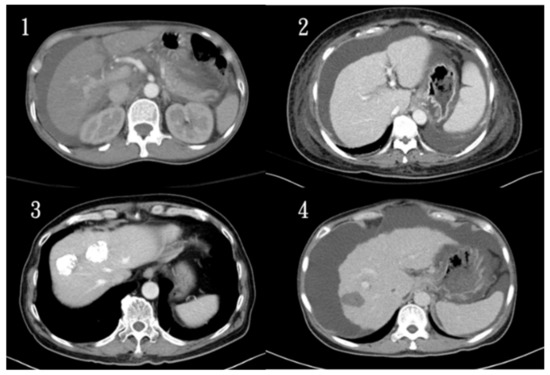

3. Liver CT Dataset